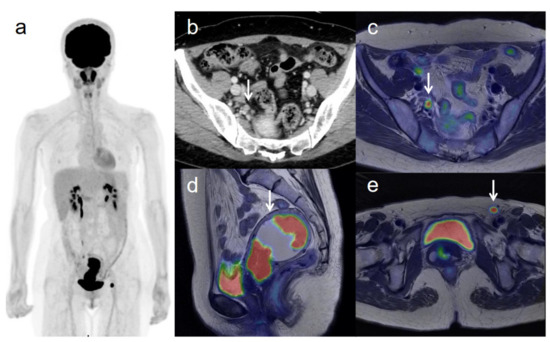

3.3. Revised FIGO Staging

Figure 3. A 53-year-old woman with IVB cervical cancer and pelvic lymph node metastasis. (a) 18F-FDG PET image shows FDG uptake by tumor in the cervical cervix (arrow) and right pelvic and left inguinal lymph nodes. (b) CT shows a right pelvic lymph node of short-axis diameter >1 cm (arrow). (c) Axial T2-weighted PET/MR image shows FDG uptake by the right pelvic lymph node (arrow). This finding is strongly suggestive of pelvic lymph node metastasis, which was confirmed by histopathologic examination. (d) Sagittal T2-weighted PET/MR image shows FDG uptake by the cervical tumor and invasion into the corpus uteri (arrow), which was confirmed by histopathologic examination. (e) Axial T2-weighted PET/MR image shows FDG uptake by the left inguinal lymph node (arrow).